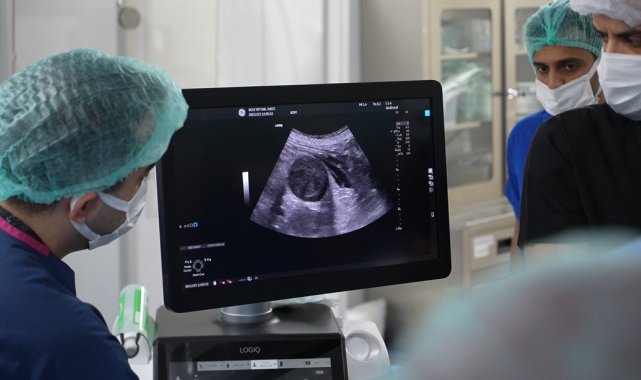

Girişimsel Radyoloji Bilim Dalı Öğretim Üyesi Doç. Dr. İsa Çam koordinesinde gerçekleşen etkinlik kapsamında, karaciğer, böbrek, tiroit ve paratiroit tümörlerinde uygulanan ve halk arasında "iğne ile yakma" olarak bilinen tedavi yöntemi, canlı vakalar eşliğinde katılımcılara gösterildi. Yaklaşık yarım saat süren operasyonla tümörün iğne deliğinden girilerek yakılması işlemi, yabancı hekimler tarafından ilgiyle takip edildi.

Artan talepler üzerine iki günlük workshop düzenlediklerini belirten Çam, "Workshopun ana amacı karaciğer, böbrek, tiroit ve paratiroit tümörlerinde ameliyatsız termal ablasyon yöntemlerini canlı vakalar eşliğinde göstermek. Bu kapsamda katılımcı hekimlere tiroit termal ablasyon işlemlerinin canlı uygulamasını gösterdik. Bölüm olarak oldukça tecrübeliyiz. Son iki yılda 500-600 vaka gerçekleştirdik. Bu bilindiği için hekimler eğitim talep ediyor. Üniversite yönetiminden ve hastalarımızdan izinleri alarak bu organizasyonu yaptık, geri dönüşler çok olumlu" dedi.